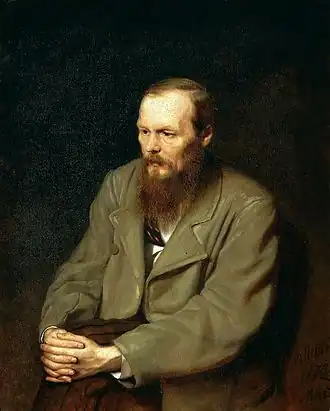

La literatura ha ofrecido una perspectiva amplia sobre enfermedades mentales y neurológicas como la paranoia, la neurosis, la histeria y la epilepsia, que puede apreciarse en la representación y significación de numerosas obras como Otra vuelta de tuerca por Henry James, La corazonada de una suerte de Fiódor Dostoyevski, así como obras de León Tolstói, Hermann Hesse, Edgar Allan Poe y María de Jorge Isaacs que narra la historia de la enfermedad hereditaria epiléptica de María, la protagonista de la historia. Dostoievski padeció epilepsia a lo largo de toda su obra literaria e hizo un uso inteligente de la misma en su literatura, incluyendo personajes o situaciones inspiradas por la misma en obras como La patrona, Humillados y ofendidos, El idiota, Los demonios, Diario de un escritor y Los hermanos Karamázov. También supo utilizar la epilepsia pragmáticamente para poder librarse de una condena vitalicia sirviendo al ejército en Siberia, obteniendo sendos informes de los doctores Troïtski (prisión de Omsk) y Ermakov (séptimo batallón de infantería de Semipalatinsk). Aunque la epilepsia había comenzado probablemente durante sus años académicos como estudiante de ingeniería militar en San Petersburgo (1838-1843), según los testimonios aportados por un compañero con quien compartía habitación (Grigorovich), el diagnóstico tardaría otra década en llegar. Ya en 1847 había sido atendido por su amigo el doctor Ianovski durante una fuerte crisis delante de la catedral de San Isaac y en 1857 fue atendido por un médico en Barnaul quien corroboró el diagnóstico. En 1863 viajó al extranjero con intención de consultar a los especialistas Romberg en Berlín y Trousseau en París. Stephenson e Isotoff apuntaron en 1935 la probable influencia de Psique (1848), de Carus, en la construcción de sus personajes. La epilepsia de Dostoyevski ha generado un debate diagnóstico retrospectivo atrayendo la atención e inspirando a neurólogos, epileptólogos y psiquiatras como Freud (1928) Alajouanine (1963) o Gastaut (1978). La de Dostoyevski es la historia natural de una epilepsia , la cual en terminología científica contemporánea podría clasificarse como criptogénica focal de presumible origen temporal. Los bromuros fueron el primer fármaco antiepiléptico en introducirse hacia mediados del siglo XIX, con efectos secundarios que superaban muchas veces su posible beneficio. En 1974, Waxman y Geschwind describieron una personalidad asociada al tipo de epilepsia que padeció el escritor, dominado por la hipergrafía y la hiperreligiosidad, posteriormente denominado síndrome de Dostoievski. En 1980, Cirignotta, Todesco y Lugaressi propusieron el término epilepsia de Dostoevsky para describir un tipo de enfermedad caracterizada por auras de éxtasis, las cuales el propio escritor había atribuido a sendos personajes de El idiota y Los demonios: una sensación placentera o de plenitud anticipándose a la pérdida de conocimiento y a las convulsiones que también había descrito a varios de sus contemporáneos (entre otros, al poeta Nekrasov). A pesar del negativo impacto que la epilepsia tuvo sobre su vida, Dostoievski fue capaz de producir obras maestras hasta el final, haciendo un buen uso de la misma para enriquecimiento de una inmensa obra, cuyo legado constituye una aportación continua al humanismo, a la literatura y a la medicina actuales.[49]